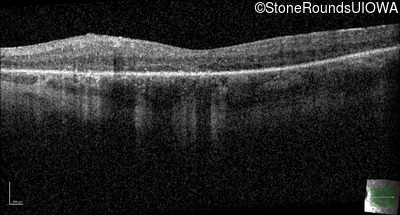

Optical Coherence Tomography - Right - 20/40

Exemplar / OCT Stack